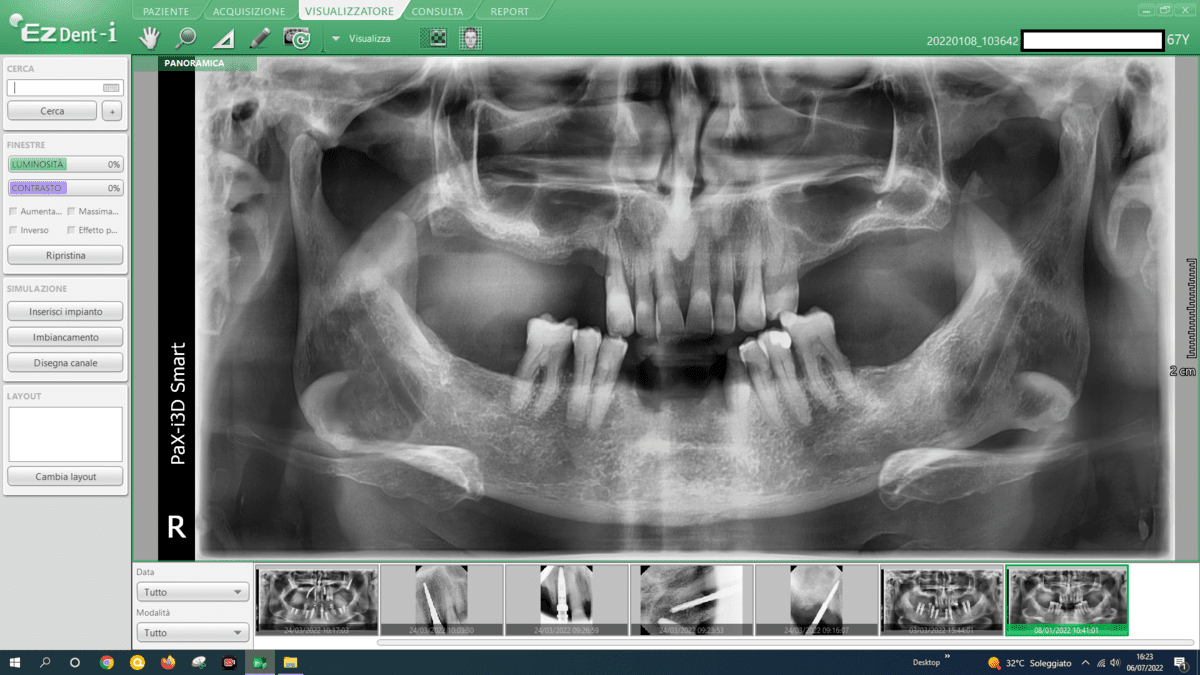

In addressing mandibular atrophies, our approach revolves around utilizing advanced implant techniques that offer superior outcomes compared to traditional methods like autologous bone grafts. Here’s a breakdown of our considerations:

- Transverse Implants:

- We employ transverse implants, strategically placed across the mandible. This technique provides stability and support, avoiding the need for extensive bone grafting.

- Blade Implants:

- Blade implants are another key component of our approach. These implants are designed for efficient insertion, providing secure anchorage in atrophic areas without the challenges associated with autologous bone grafts.

- Grid-Like Subperiosteal Implants:

- Our practice utilizes subperiosteal implants configured in a grid-like pattern. This innovative approach optimizes bone contact, ensuring a strong foundation for the implants. This technique eliminates the necessity for autologous bone grafts and their associated complexities.